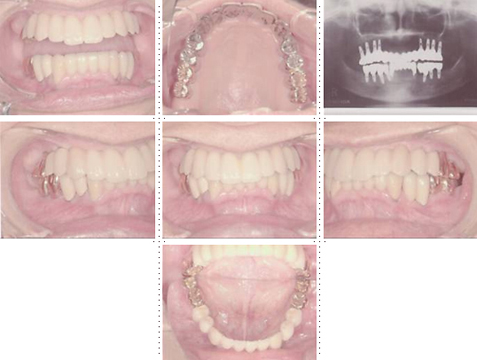

症例3

73才 男性

上顎2本、下顎1本だけ歯が残り、入れ歯を使っておりますが、痛みがありよく噛めない状態。

上顎1本の歯だけを残し、インプラント8本埋入。下顎は歯を抜き、インプラント7本埋入。上下顎とも、セラミック(MB)クラウンをセット。仕事・生活ともに活力が出て、新しい人生が始まったようであると喜んでいただきました。